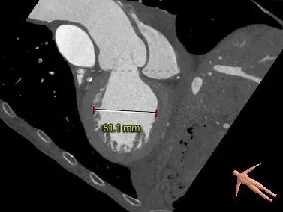

主动脉根部测量

Annulus

24.7mm

VR图

SOV:

41.0*40.9*47.6mm

STJ:

39.1mm

AAO:

40.1mm

三叶瓣,系纯反流患者,环周长折算直径24.7mm;